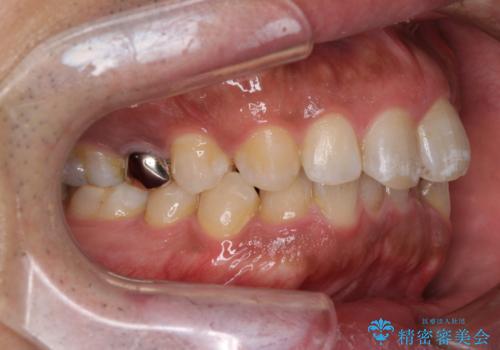

レントゲン撮影により、右上奥歯が折れていることが分かりました。

患者様自身も何となく違和感を覚えていたとのことで、インプラント補綴治療を行うこととしました。

破折して抜歯が必要となった歯の後ろの歯は、根管治療が必要な状態であったので、根管治療を行い、矯正治療後にインプラント部の補綴治療と同時にセラミッククラウンを装着しました。

矯正治療以外に費用負担がかかることになりましたが、気になるところ全てを処置することができ、患者様には大変満足していただきました。